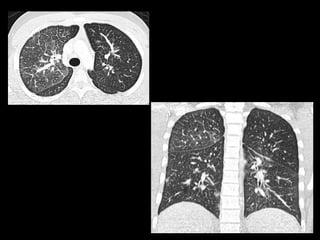

This document discusses 4 unknown pediatric radiology cases presented by Dr. Kirsten Ecklund from Boston Children's Hospital. Case 1 involves a 7 year old boy with fatigue, knee pain and swelling. Case 2 is a 15 year old African American male with cough, shortness of breath and 10 pound weight loss. Case 3 is an 8 year old boy with abdominal pain, distention and vomiting. Case 4 is an 11 year old boy with 6 months of bilateral knee pain greater on the right side.